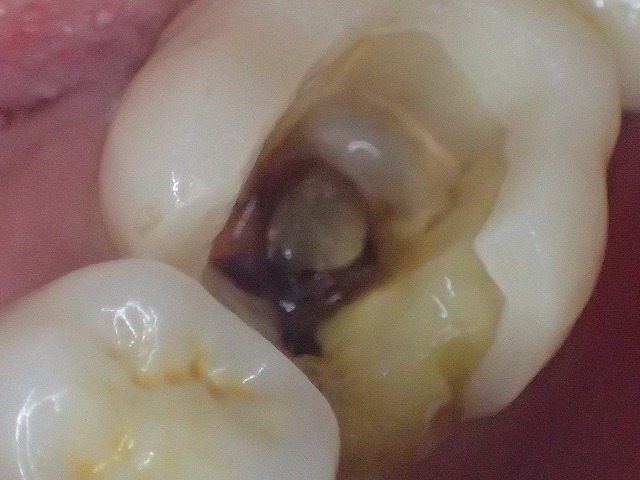

下の画像は髄空の角が出たところです。

この段階で大きく二次象牙質が形成されているのが分かります。

髄腔の真ん中に二次象牙質の塊があります。

これを「象牙真珠」と呼びます。